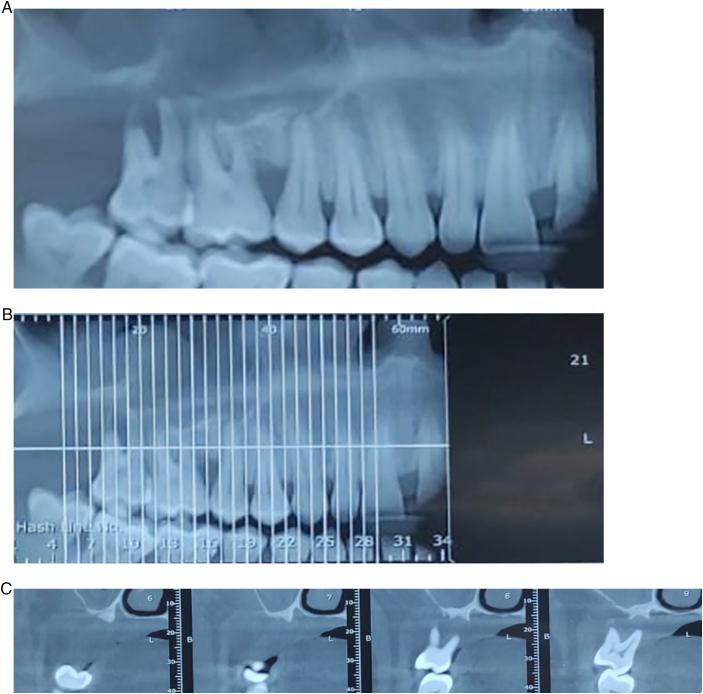

Female patient 38 years old, complain of mobility of upper right 7 with dull pain and swelling related to it. She also mentioned that the upper wisdom molar at the same side was extracted a year before due to the same reason. Extraction of upper right 7 and excisional biopsy of surrounding soft tissue swelling and by laboratory investigation and analysis to the biopsy we found that the lesion is gingival plasmacytosis. Microscopic examination revealed marked squamous hyperplasia with focal ulceration and diffuse dense subepithelial plasmacytic infiltrate consistent with PCG. At higher magnification, plasma cells were seen without cellular atypia. The individual plasma cells had eccentric round nuclei with cartwheel chromatin patterns and abundant cytoplasm.